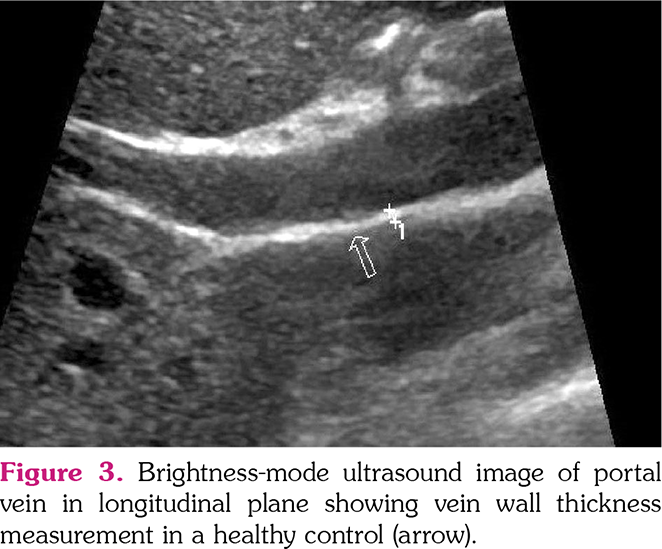

All US examinations were performed by an aboard-certified radiologist with seven years of experience in US imaging who was blinded to cases on the same day with clinical assessment. A second radiologist with an experience of three years in US imaging performed IMT and VWT measurements of the first 20 individuals on the same day with the first radiologist to evaluate the inter-observer agreement. All US examinations were performed after a fasting period of 6 h. Bilateral CIMT, jugular vein, and common femoral VWTs were measured using a 4-15-MHz ML6-15 linear transducer (Logiq E9, General Electric Company, Fairfield, CT, USA). mesenteric, The portal vein, inferior vena cava, superior renal, and splenic VWTs were measured using a 2-8-MHz 9L-D linear transducer (Logiq E9, General Electric Company, Fairfield, CT, USA). US examinations were performed with a high-resolution US system (LOGIQ E9; GE Healthcare, Wauwatosa, WI, USA). VWTs were evaluated during the Valsalva maneuver and IMT was measured during neutral breathing in the supine position. All veins were evaluated in both longitudinal and transverse planes. CIMT was automatically measured in a longitudinal axis using the Auto-IMT application (GE Healthcare, Wauwatosa, WI, USA). Three measurements were performed by the observers from each vessel and the average of these measurements for each vessel was noted (Figures 1-3).

The diagnostic performance of VWT for vascular involvement in BD patients was evaluated by ROC analysis. When the cut-off value was taken as 1.35 mm for portal VWT, the sensitivity and specificity for vascular involvement were 79.2% and 82.4%, respectively (area under the curve [AUC]=0.869, 95% confidence interval [CI], 0.783-0.956) (Table 4, Figure 4). When the cut-off value was taken as 0.75 mm for the right common femoral vein, the sensitivity and specificity were 66.7% and 56.9%, respectively (AUC=0.706, 95% CI, 0.583 to 0.829) (Table 4, Figure 4). The sensitivity and specificity of the VWTs and their predictive values are shown in Table 4.

Early recognition of vascular involvement improves morbidity and mortality in BD.[2] In our study, it was found that portal VWT was significantly higher in BD patients with vascular involvement compared to those without vascular involvement, and its sensitivity and specificity for the diagnosis of vascular involvement were 79% and 82%, respectively, when the cut-off value was taken as 1.35 mm. The cut-off value obtained may be a guide for screening vasculo-BD. However, there is a need for large-scale prospective studies to verify this result.

In conclusion, portal VWT was higher in BD patients with vascular involvement compared to those without vascular involvement and healthy controls. Our results suggest that portal VWT measurement with US, a non-invasive radiological imaging modality, might be used as a screening tool for vasculo-BD with sensitivity and specificity values higher than 75% for the cut-off value ≥1.35 mm.